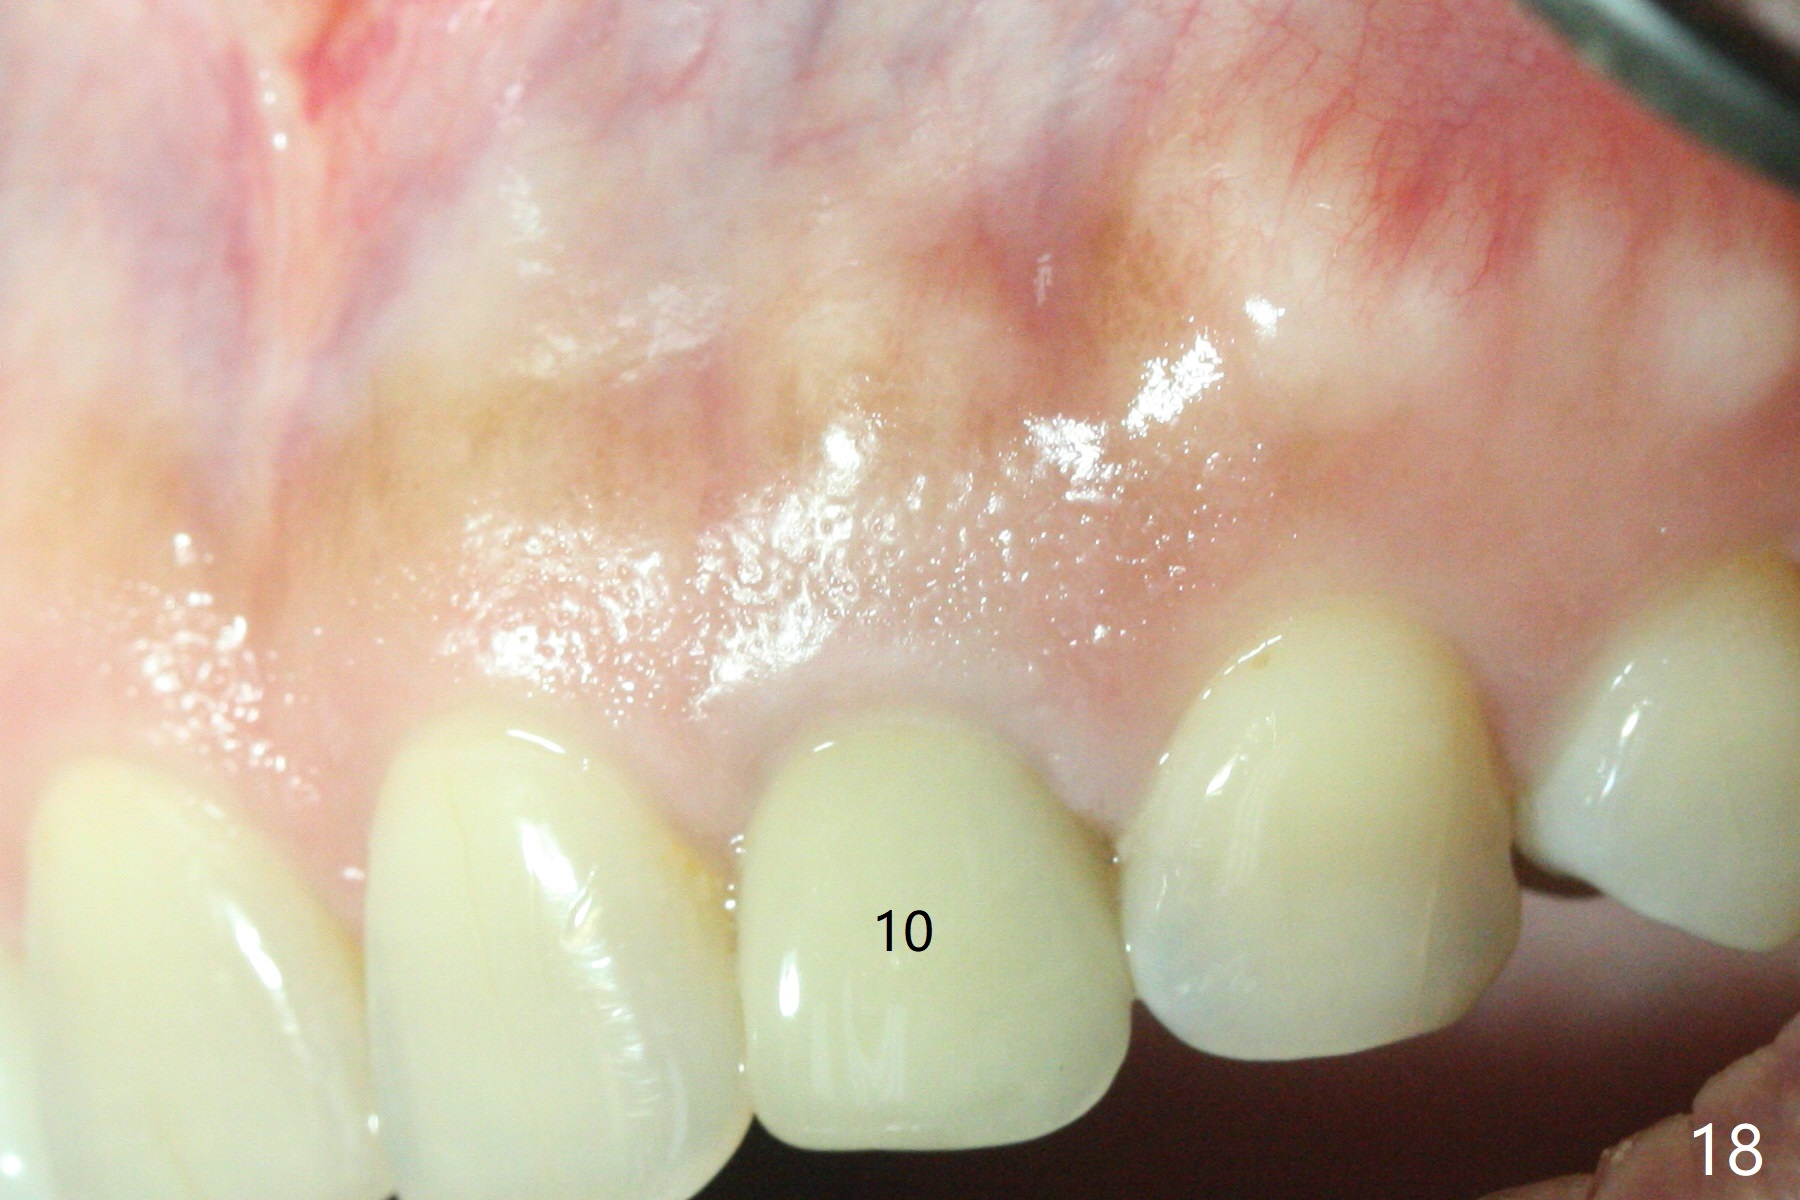

The gingival architecture around the immediate provisional is normal 5 months postop (Fig.10,12). To increase cosmetics for the definitive restoration, the abutment length is reduced (compare arrowheads in Fig.11 to 12).

Dense bone forms immediately next to the implant 3 years 5 months post cementation (Fig.13) without gingival recession (Fig.14,15). In fact, the buccal plate maintains root contour over the implant (Fig.15 *). The root prominence remains 6 years 3 months post cementation (Fig.16-18 *). Appreciate the labial concavity associated with implant placement 6 years 9 months post cementation (Fig.19). The implant must have been placed quite palatal.